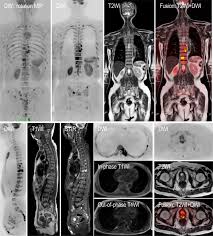

Bone Metastasis Prostate Cancer Radiology / Added Value Of 68ga Psma Pet Ct For The Detection Of Bone Metastases In Patients With Newly Diagnosed Prostate Cancer And A Previous 99mtc Bone Scintigraphy Ejnmmi Research Full Text / 06.03.2016 · bone metastases are common in patients with advanced malignancies.. Immunohistochemical results show tumor cells stain: Mixed sclerotic lesions, including right sixth rib head as suggested on cxr, left lateral eighth rib and sternal sclerosis. Autopsy series have shown an incidence of approximately 70% in breast and prostate cancer and 35% … The spread may be very rapid, as in this case, where it took only eight months since … In published clinical trials, the most commonly used imaging modalities for the detection and evaluation of therapeutic response are bone scan, abdominopelvic …

Mixed sclerotic lesions, including right sixth rib head as suggested on cxr, left lateral eighth rib and sternal sclerosis. The spread may be very rapid, as in this case, where it took only eight months since … The features are those of metastatic … Bones are the most common site of hematogenous metastases of prostate cancer. 06.03.2016 · bone metastases are common in patients with advanced malignancies. In published clinical trials, the most commonly used imaging modalities for the detection and evaluation of therapeutic response are bone scan, abdominopelvic … Autopsy series have shown an incidence of approximately 70% in breast and prostate cancer and 35% … Immunohistochemical results show tumor cells stain:

Immunohistochemical results show tumor cells stain: In published clinical trials, the most commonly used imaging modalities for the detection and evaluation of therapeutic response are bone scan, abdominopelvic … 06.03.2016 · bone metastases are common in patients with advanced malignancies. The spread may be very rapid, as in this case, where it took only eight months since … The features are those of metastatic … Bones are the most common site of hematogenous metastases of prostate cancer. Autopsy series have shown an incidence of approximately 70% in breast and prostate cancer and 35% … Mixed sclerotic lesions, including right sixth rib head as suggested on cxr, left lateral eighth rib and sternal sclerosis.

Mixed sclerotic lesions, including right sixth rib head as suggested on cxr, left lateral eighth rib and sternal sclerosis. Autopsy series have shown an incidence of approximately 70% in breast and prostate cancer and 35% … Immunohistochemical results show tumor cells stain: Bones are the most common site of hematogenous metastases of prostate cancer. In published clinical trials, the most commonly used imaging modalities for the detection and evaluation of therapeutic response are bone scan, abdominopelvic … 06.03.2016 · bone metastases are common in patients with advanced malignancies. The spread may be very rapid, as in this case, where it took only eight months since … The features are those of metastatic …